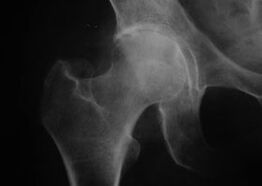

Koxatróza, artróza kyčelního kloubu

U tohoto onemocnění je pozorován klasický klinický obraz artrózy.

Prvním příznakem koxartrózy je nepohodlí v kyčelním kloubu po fyzické aktivitě.

Při progresivní koxartróze narůstá bolest, objevuje se ztuhlost a omezená pohyblivost.

Pacienti s těžkou formou koxartrózy šetří postiženou končetinu, vyhýbají se šlápnutí na ni a ve stacionárním stavu volí polohy, ve kterých je bolest nejméně pociťována.